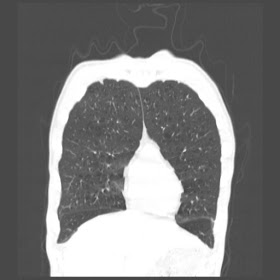

A 52 Years old man suffering with chest pain since 3 years

HRCT Chest